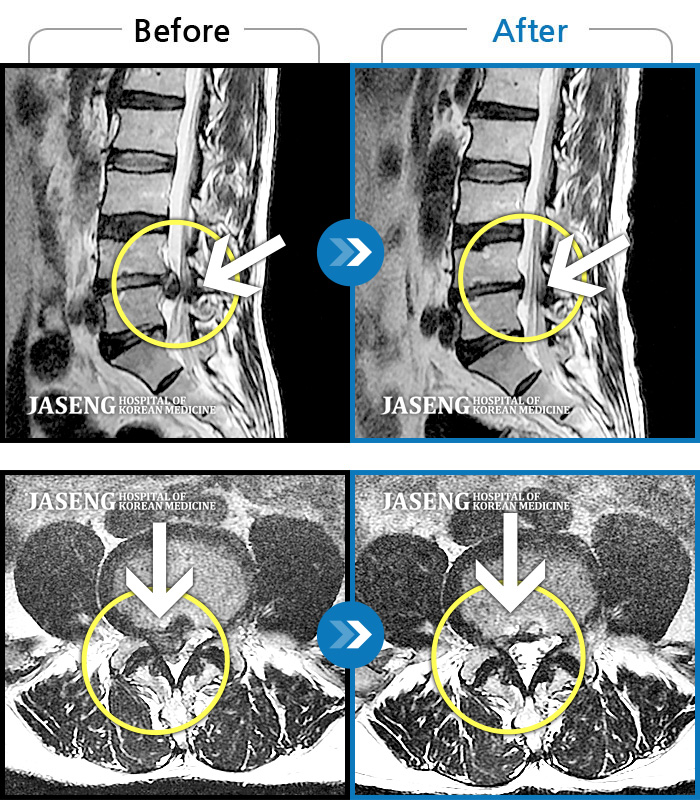

저는 척추협착과 전방위 증으로 10분도 못 걸었습니다

열심히 침과 약침 을 놓아 주셔서 지금은 그래도 걷는데 전보다는 많이 나아진 상태로

처음엔 몇 발작도 못가 주저 앉고 싶은 통증이었는데 지금은 계단도 잡지 않고 걸을수 있으니